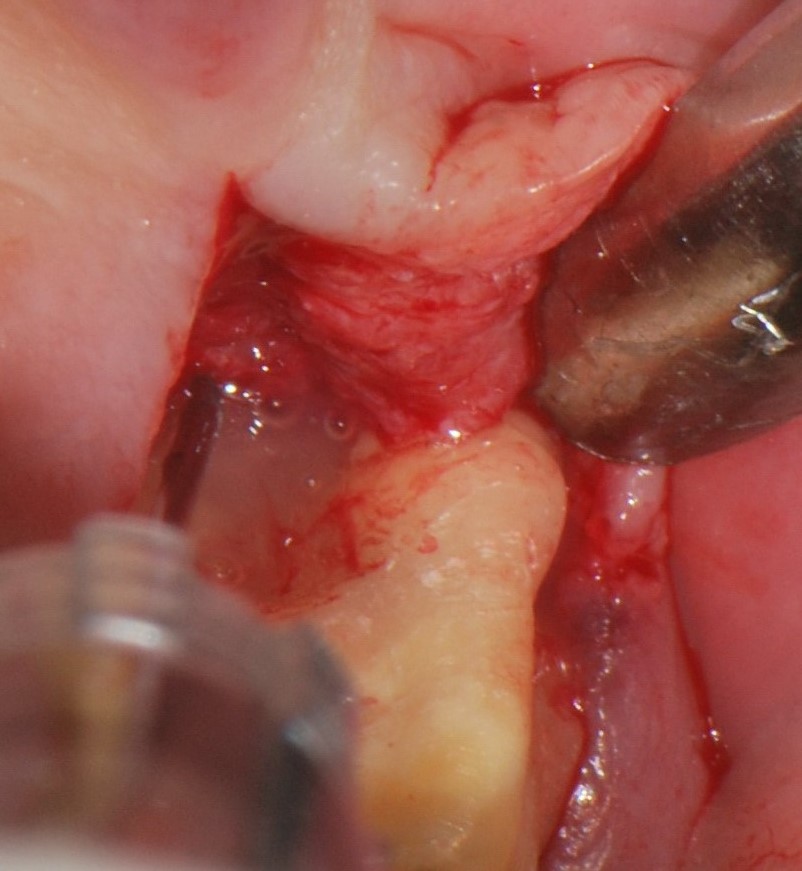

04/06 - Flap elevation by a midcrestal incision and application of Straumann® Emdogain® to the defect site.Treatment of a periodontal bone defect adjacent to an edentulous site using Straumann® Emdogain® - Prof. Dr. P. Windisch